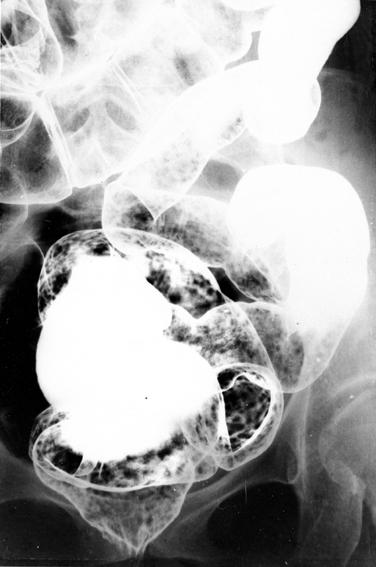

Criteria of Hist.ClassificationTumor-like lesions/Benign lymphoid polyposis

LocationLarge intestine(Colon)/More than one of the above

Technique, MethodX-ray

Size1 - 9